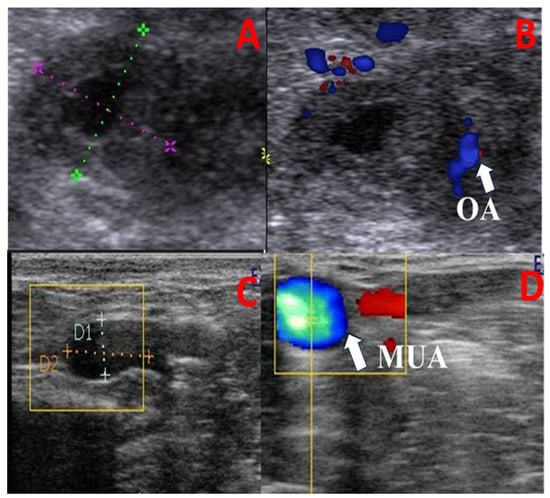

- Hemodynamic changes within the MUA on the ipsi- and contra-lateral sides of the uterine horn at its origin (the internal iliac artery) and within the OA corresponding to the ovarian tissues were monitored as previously reported [29,30] (Figure 2). In brief, once the MUA was visualized via B-mode ultrasonography, blood flow was affirmed using the Doppler device color mode, followed by pulsed-wave mode activation for Doppler index measurement. All calculations were determined automatically by the device and measured three times to obtain the mean by the same person. At least three successive waves (cardiac cycles) were estimated to measure the Doppler parameters with calibrated and fixed Doppler settings throughout the study, as follows: The pulse repetition frequency was 3.5 KHz, the angle of insonation was less than 60 °, and the color flow mapping included two colors (red and blue; Figure 2). Examined blood flow parameters were the pulsatility index (PI), resistance index (RI), peak systolic/end-diastolic ratio (S/D), time-averaged maximum velocity (TAV; cm/s), uterine blood flow rate (BFR; bpm), and uterine blood flow volume (BFV; mL/min). BFV was estimated using the following equation: BFV = TAV(cm/s) × (D(cm) × 0.5)2 × π 60 [22].